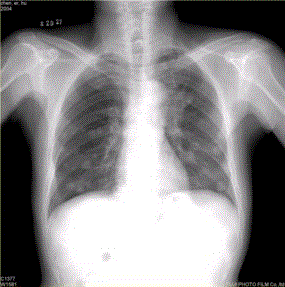

问题 患者男,45岁,因肝硬化、肝癌行肝移植术后6个月,咳嗽2周,来院复查。CR及CT影像如下图。 该疾病的转移途径可以为

选项 A.经肺动脉 B.经肺动脉至淋巴管而后到肺外围 C.经纵隔淋巴结逆流到肺门淋巴结,再经肺内淋巴管到肺外周 D.经胸膜腔 E.经气道 F.经支气管动脉

答案 ACDE